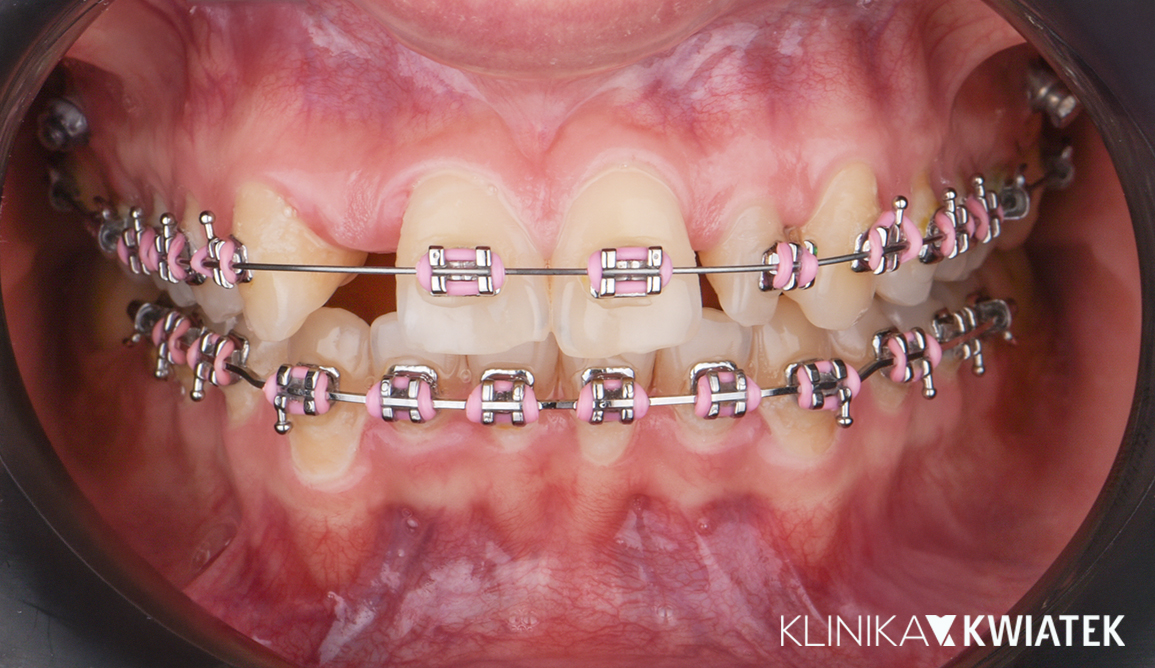

Luksus dyskretnej ortodoncji oparty na zaawansowanej technologii nakładkowej

Pacjentka zgłosiła się do kliniki z potrzebą kompleksowej poprawy zarówno funkcji zgryzu, jak i estetyki uśmiechu. W badaniu stwierdzono zgryz krzyżowy, stłoczenia zębów oraz liczne problemy wymagające leczenia zachowawczego i protetycznego, co wymagało wieloetapowego, interdyscyplinarnego podejścia. Terapię poprzedziło staranne przygotowanie jamy ustnej obejmujące ekstrakcję zębów mądrości, profesjonalną higienizację oraz odbudowę osłabionych struktur. Następnie wdrożono zaawansowane leczenie ortodontyczne z wykorzystaniem nowoczesnego systemu nakładkowego. Rezultatem jest harmonijny, stabilny zgryz, idealnie ukształtowane łuki zębowe oraz wyraźnie odmłodzony, jasny uśmiech, podkreślony profesjonalnym wybielaniem.